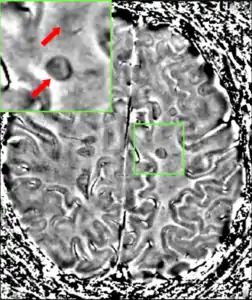

Central vein signs (CVS) have been proposed as a good indicator of MS in comparison with other conditions causing white lesions.[64][65][66][67] One small study found fewer CVS in older and hypertensive people.[68] Further research on CVS as a biomarker for MS is ongoing.[69]